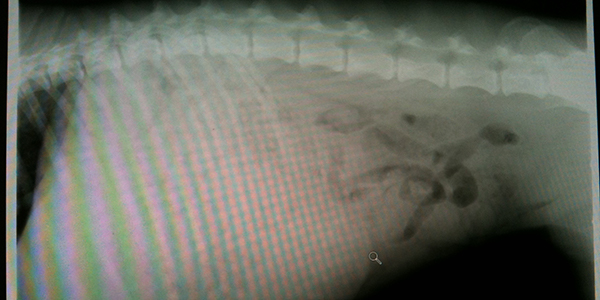

Once your dog is at the veterinary hospital, your doctor will do a physical exam, and an X-ray will be taken. Food bloat shows up as large amounts of food visible in the stomach. This helps distinguish it from GDV, which is usually just air in the stomach.

A bloated stomach from overconsumption of food will be very dilated (swollen) on an X-ray. This stomach (featured in the photo above) is FULL of digested food, which makes it difficult to see the other organs or intestines.

Occasionally, you may see some gas in the intestines, like in this x-ray that shows up as what appears to be snake-like black loops. Gas or air is black on an X-ray, whereas anything soft, such as food or tissue, is grey, and bone is white. The AFTER photo below is what came out after the veterinary team induced vomiting.